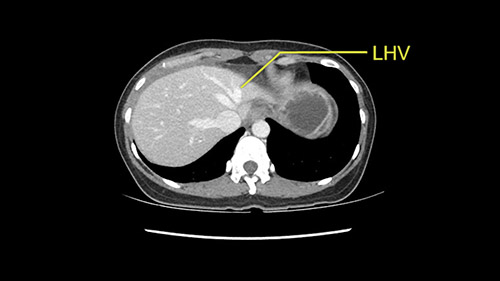

Anatomically, to plan for a left lateral segmentectomy, it’s relatively easy as far as liver surgery goes. I know that I'm going to be looking for the left hepatic vein which will be divided at some point either towards the end at the back near the vena cava or through the middle of the left lateral segment.

The transection line will be a little more obvious. There’s a little patch of focal fat here in Segment 4b but we’ll describe the transection line probably through the mid portion of Segments 4a and b up to the top. Up at the top, the left hepatic vein can be taken. There’s a Segment 3 vein or the so-called falciform vein it’ll be rudimentary so I think we’ll be able to get around the left hepatic vein and leave the middle [hepatic] vein intact because it’s free of tumor.

Her vein, it looks like a combined middle and left hepatic vein, it may be encircled during the case as a whole common trunk but most probably it will not be a big deal because if it is okay to go with the left lateral resection, the vein or the left hepatic vein can be catched during the intraparenchymal dissection and can be controlled in that side.

The other option of course is to do an anatomical left hepatectomy. In that case, I will start mobilizing of course the left lobe and try to find the ligamentum venosum, take it down and go around the left hepatic vein. I think, importantly in these cases and in this case, as you can see in the venous phase, that’s clearly a moment to stop. Because the left hepatic vein is pretty close to the middle hepatic vein as sometimes it is so you may need to dissect a little bit the parenchyma on top of the left hepatic vein to be able to go around the left hepatic vein safely.